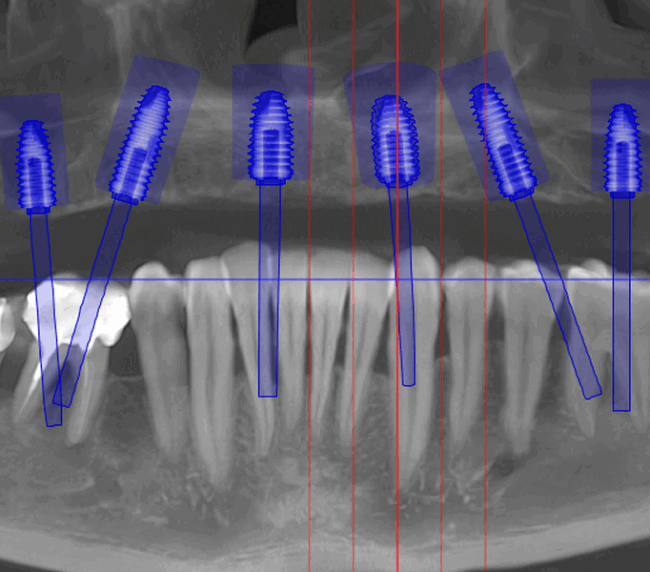

- Investigație imagistică completă, ideal CBCT (computer tomografie);

- Planificare computerizată a intervenției, inclusiv realizarea și utilizarea ghidului chirurgical, dacă este necesar;